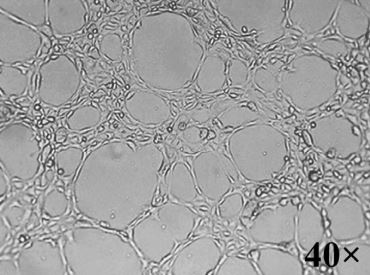

Bottom Image: Neuromics HBMECs forming tubules on Matrigel